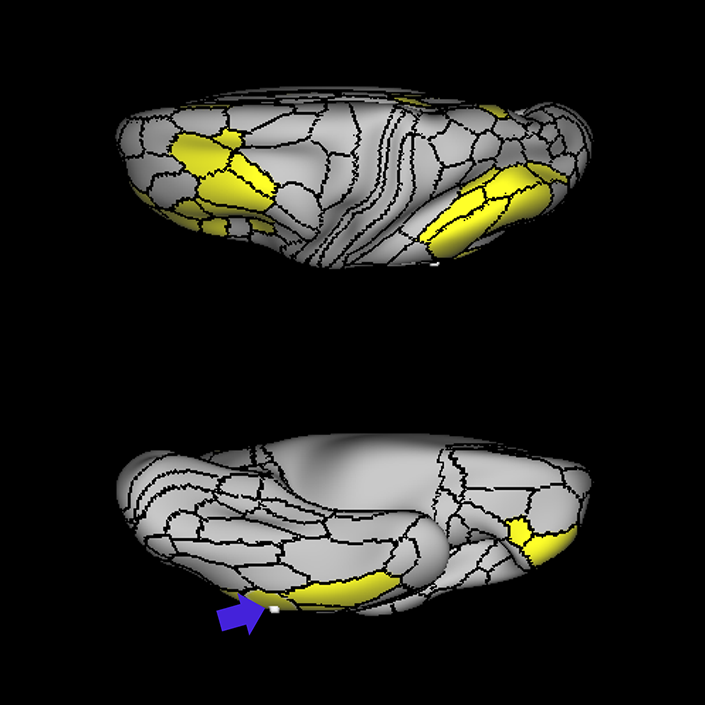

ᐅ SummaryArea 45: part of the inferior frontal gyrus of the lateral frontal lobe. In addition to its known association with Broca's area, is sometimes represented as part of Broca's complex ᐅ Where is it?Area 45 is the lateral surface of pars triangularis of the IFG. ᐅ What are its borders?Area 45 borders area 47L anteriorly and area 44 posteriorly. Its superior edge borders area p47r, IFSa, and IFSp. Its opercular surface is conveniently named FOP5 ᐅ What are its functional connections?Area 45 demonstrates functional connectivity to areas SFL, IFSp, 44, a47r, 47s, 47L, 9a, 9p, 9m, 8AV, and 8BL in the dorsolateral frontal lobe, area 8BM in the medial frontal lobe, area 55b in the premotor areas, areas FOP5, and PSL in the insula-opercular region, areas TGd, TGv, TE1a, STSva, STSdp and STSvp in the temporal lobe, area PGi in the inferior parietal lobe, and area 31pd in the medial parietal lobe. ᐅ What are its white matter connections?Area 45 is structurally connected to the arcuate/SLF and IFOF. However, arcuate/SLF connections are not consistent across individuals. Connections with the arcuate/SLF project posteriorly and wrap around the Sylvian fissure to the middle temporal gyrus to end at TE1p. There are also projections from the arcuate/SLF before it terminates to parcellations A4 and PBelt. IFOF connections travel from 45 through the extreme/external capsule and continue posteriorly through the temporal lobe to end at occipital lobe parcellations V1, V2, V3 and V4. Local short association bundles connect with 44 and FOP4. ᐅ What is known about its function?Area 45, in addition to its known association with Broca's area, is sometimes represented as part of "Broca's complex", including Brodmann Areas 45, 46, 47 and the mesial supplementary motor area of 6, which contribute to a frontal-subcortical circuit. |

A: lateral-medial

B: anterior-posterior

C: superior-inferior

DTI image |